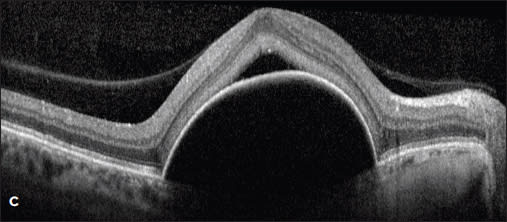

Figure 3. A patient with a new serous PED and CNV identified by ICG was treated with ranibizumab, followed by monthly aflibercept (A and B). Despite treatment, the PED worsened with increasing size and SRF (C). The patient then underwent PDT to the area of the choroidal feeder vessel without resolution (D).

Case 4. Such was the case of a 56-year-old woman who presented with a large serous PED with small amount of subretinal fluid (Figure 4A). Her vision had dropped from 20/20 to 20/400. Fluorescein angiography revealed a notch at the inferior-temporal border of the PED. ICG angiography showed a large, dilated vessel at 7 o’clock (Figure 4B).

The patient was treated with intravitreal aflibercept without improvement and then was switched to intravitreal ranibizumab. Despite treatment, the PED grew in size, and the subretinal fluid increased (Figure 4C). She was re-evaluated with ICG angiography (Figure 4D), and then was treated with PDT to the area of the choroidal vessel identified at 7 o’clock.

Four months later, the PED was unchanged, and she was retreated with PDT in combination with her monthly aflibercept. One month after the second PDT, her vision and exam remained unchanged.